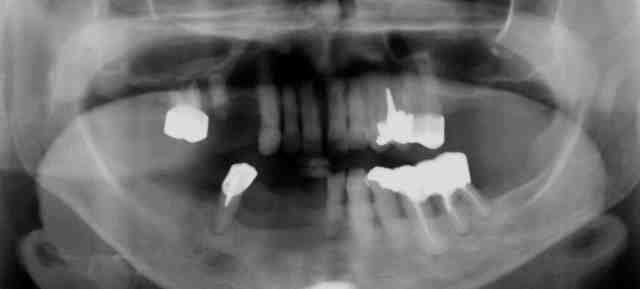

Voilà la pano et les coupes de scan de la dent 44 à 35.

Pano jj5e6o - Eugenol